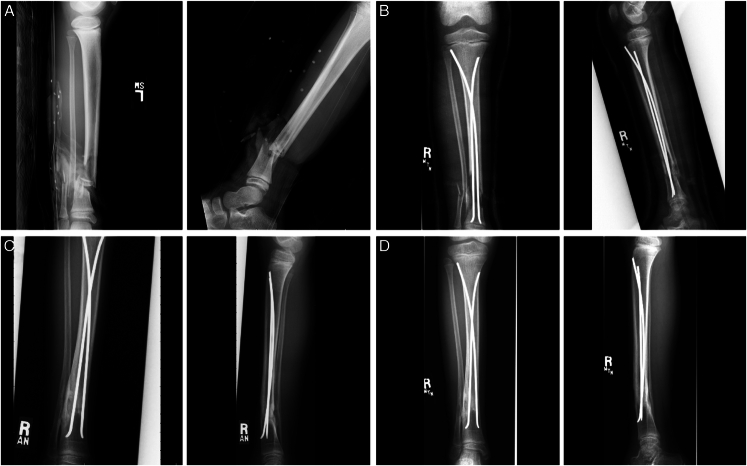

Abstract Image